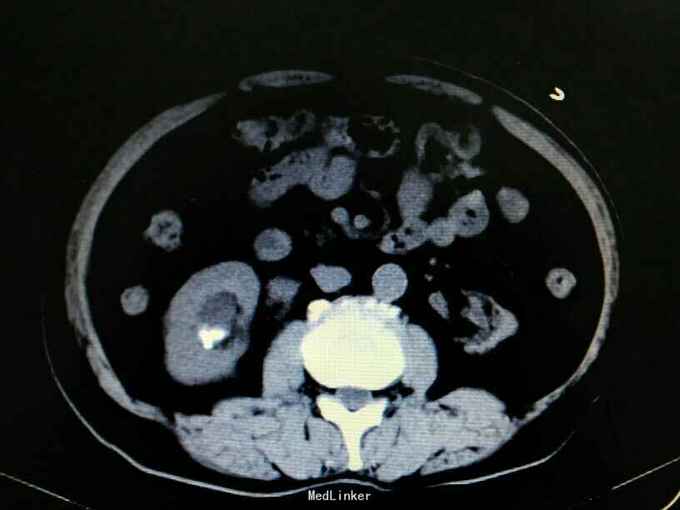

双肾铸型结石伴左肾萎缩一例

72岁男性,因“体检发现双肾结石1月”。既往10年前因双肾结石行双侧肾盂切开取石术(具体不详)。4年前因右肾输尿管结石行右侧输尿管碎石术。

双肾区叩痛。尿常规白细胞1500个/ul,两次尿培养阴性。左肾GFR15右侧38.9。

双肾铸型结石 左肾萎缩,尿路感染,双肾盂切开取石术后,BPH。经抗感染等治疗后,现在尿常规白细胞395.4个/ul。